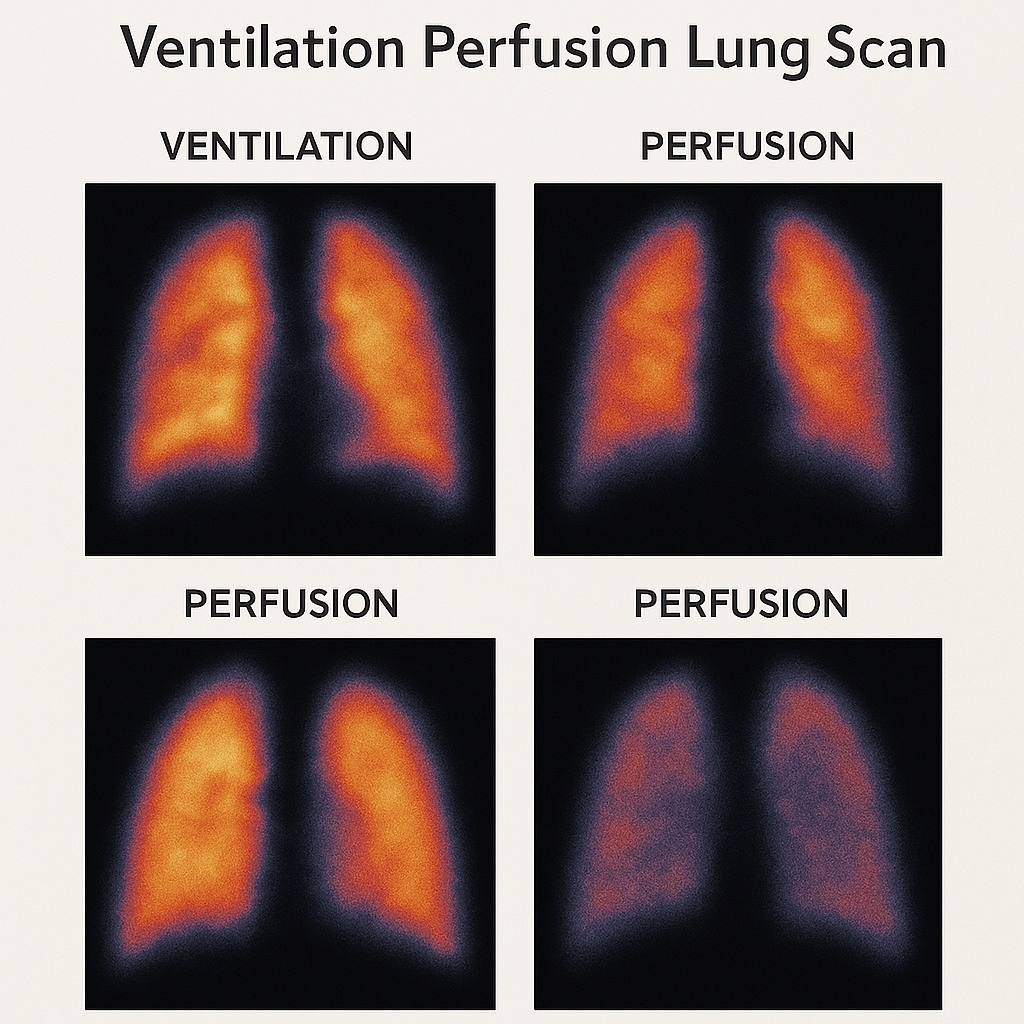

Ventilation perfusion lung scan (વેન્ટિલેશન પરફ્યુઝન લંગ સ્કેન):

- વેન્ટિલેશન પરફ્યુઝન લંગ સ્કેન એ ન્યુક્લિયર મેડીસિન ટેસ્ટ છે જેની મદદથી લંગના એર ફલો અને બ્લડ ફલોને ઇવાલ્યુટ કરવામાં આવે છે.

- જેમાં રેડિયોએક્ટિવ સબટન્સને ઇન્હાલ કરવામાં આવે છે અને તેની મદદથી એર ફલો જાણવામાં આવે છે. તેવીજ રીતે ઇન્ટ્રાવેન્સ્લી રેડિયોએક્ટિવ સબટન્સ એડમિન્સ્ટર કરવામાં આવે છે જેથી બ્લડ ફલો જાણી શકાય.